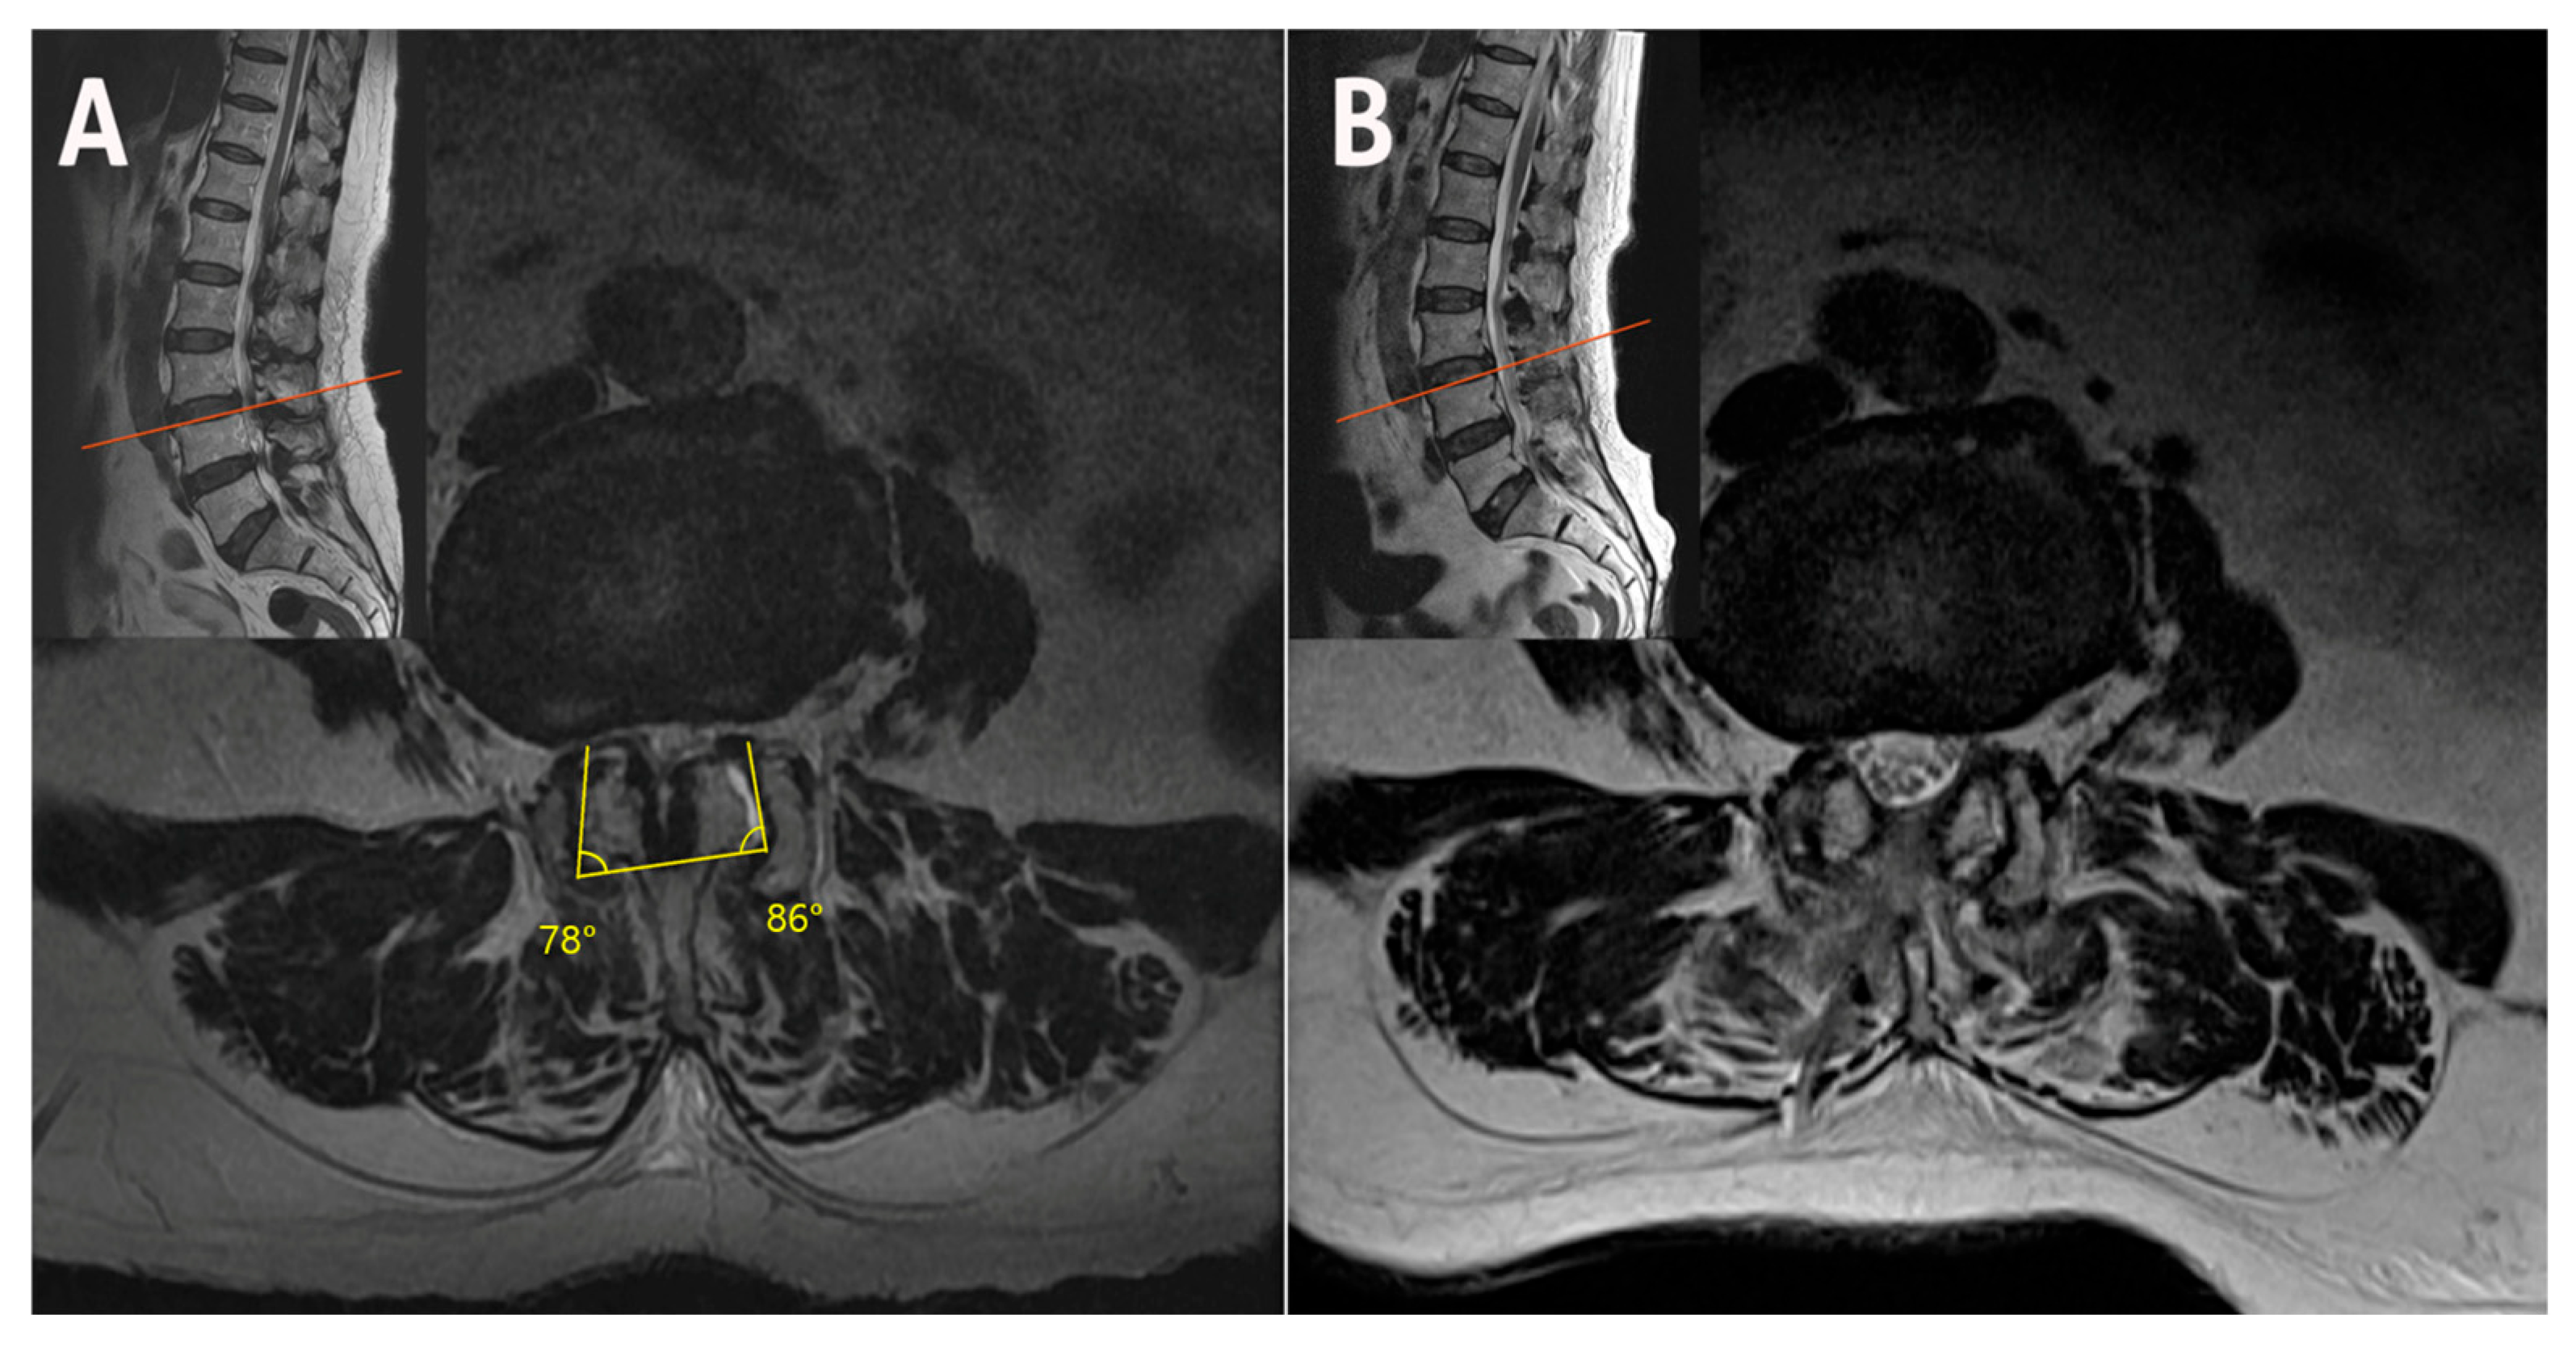

2.1. Case 1: Bilateral–Contralateral Decompression in Upper Lumbar Stenosis

2.3. Case 3: Bilateral–Contralateral Decompression in Spondylolisthesis